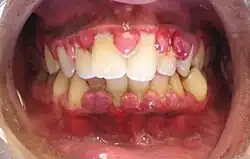

A severe case of gingivitis

Gingivitis is a non-destructive disease that causes inflammation of the gums;[1] ulitis is an alternative term.[2] The most common form of gingivitis, and the most common form of periodontal disease overall, is in response to bacterial biofilms (also called plaque) that are attached to tooth surfaces, termed plaque-induced gingivitis. Most forms of gingivitis are plaque-induced.[3]